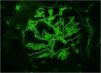

Renal biopsy was performed. Light microscopy demonstrated focal necrotizing crescentic glomerulonephritis with cellular and fibrous crescents (Fig. 1). 40% of glomeruli were globally sclerotic. Immunofluorescence microscopy demonstrated linear (2+) staining along the glomerular capillary loops for IgA (Fig. 2) along with weak linear staining for IgG, anti-kappa and anti-lambda antibodies. Interstitial fibrosis and tubular atrophy occupied 40% of renal parenchyma. By electron microscopy there were no immune complex-type deposits. The findings were consistent with IgA-mediated anti-GBM disease.